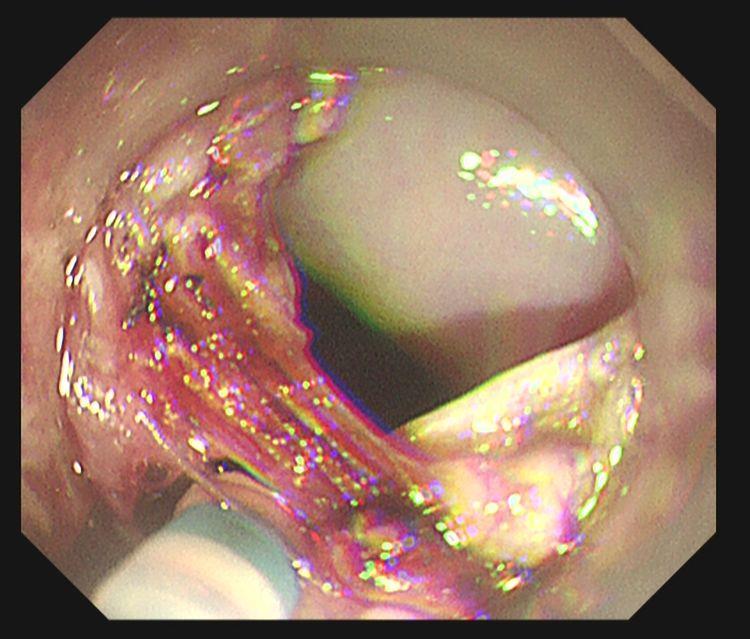

完整剥离病灶